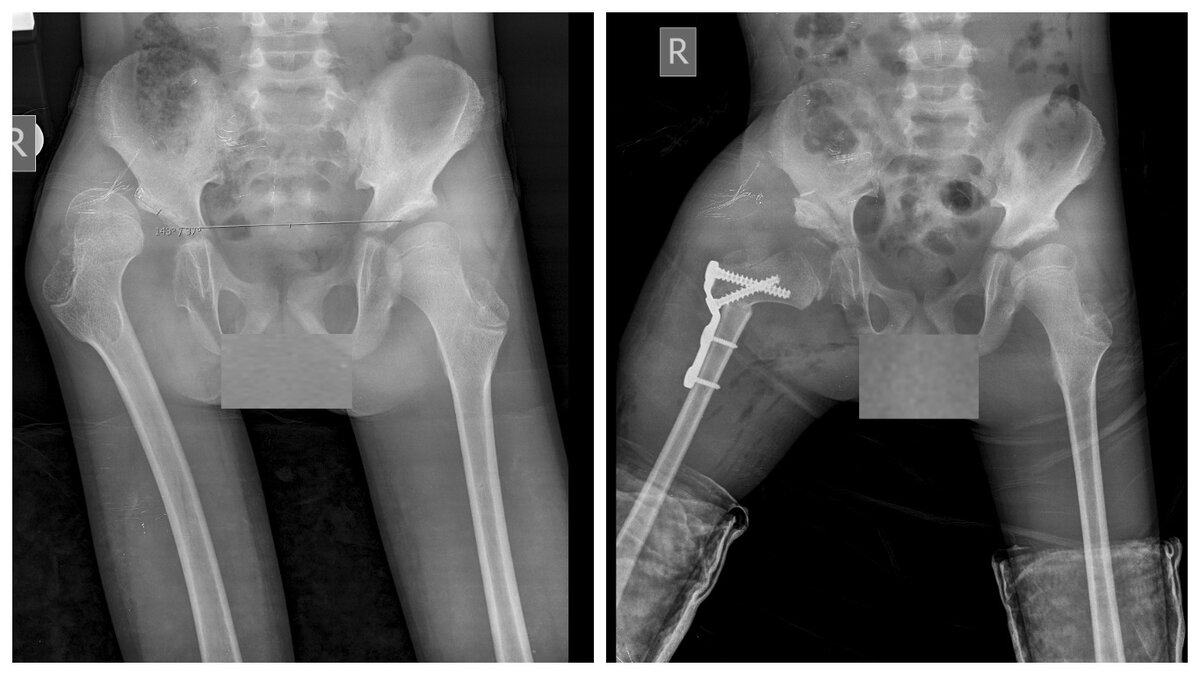

Ситуация сложнее, когда разрушения происходят в тазобедренном суставе, и об условно-реконструктивной хирургии речь уже не идет. Когда головка бедра потеряла суставной хрящ и костные структуры под ним, ее форма больше не округлая, вертлужная впадина деформирована, уплощена, технически можно восстановить взаимоотношения головки бедра и вертлужной впадины, привести их в контакт, но это лишь усилит болевой синдром даже при пассивных движениях. В данной ситуации выполняют ПАЛЛИАТИВНЫЕ ОРТОПЕДИЧЕСКИЕ ОПЕРАЦИИ. В случае, когда бедро находится в состоянии приведенного сгибательного положения, и на фоне выраженного болевого синдрома малейшие движения и минимальные гигиенические процедуры вызывают у ребенка сильные страдания, задача хирургии не восстановление правильных взаимоотношений в тазобедренном суставе, а УСТРАНЕНИЕ БОЛЕВОГО СИНДРОМА И ВОЗМОЖНОСТЬ ПАССИВНЫХ ДВИЖЕНИЙ на отведение и сгибание ноги, пассивной вертикальной позы, комфортной позы сидя.

Цель паллиативных ортопедических операций не анатомическое восстановление сустава, а создание благоприятных условий для пассивной мобилизации ребенка, снижение болевого синдрома и улучшение качества жизни ребенка с ДЦП.